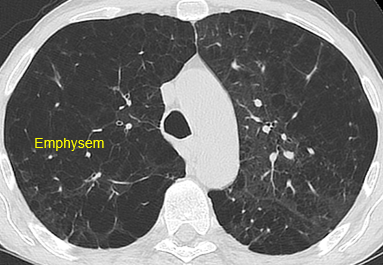

Beispielhafte Aufnahmen verschiedener Erkrankungen

(Lungenklinik Lostau)

Chronisch obstruktive Lungenerkrankung (COPD) und Emphysem – CT-basierte Beurteilung

Bei der chronisch obstruktiven Lungenerkrankung (COPD) und beim Emphysem kann die Computertomographie (CT) helfen, Ausprägung und Verteilung der Veränderungen zu beurteilen. In geeigneten Fällen unterstützen quantitative Auswertungen die Therapieplanung und Verlaufskontrolle.